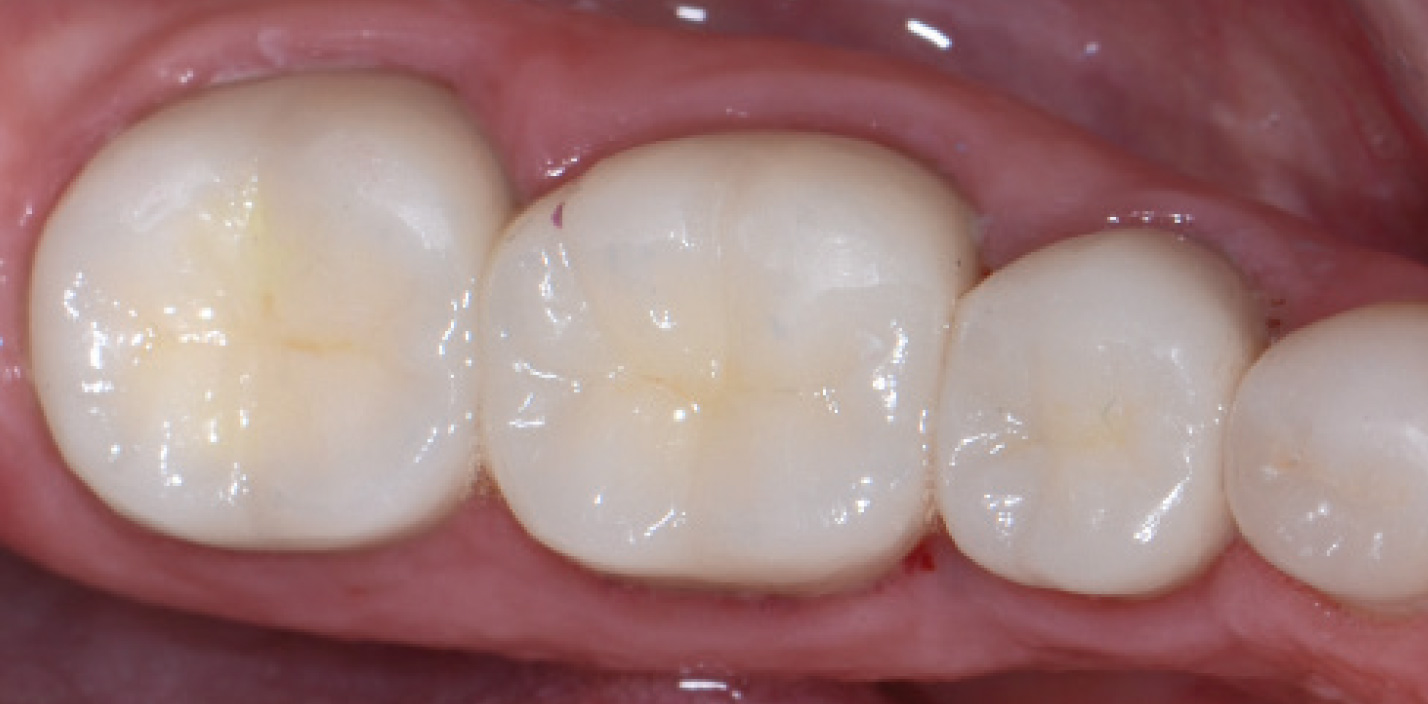

Full-coverage lithium disilicate crowns luted with a self-curing resin-based dental luting material with a light-curing option (Multilink® Automix, Ivoclar Vivadent, www.ivoclarvivadent.com). Ceramics by Gold Dust Dental Lab.

Figure 1